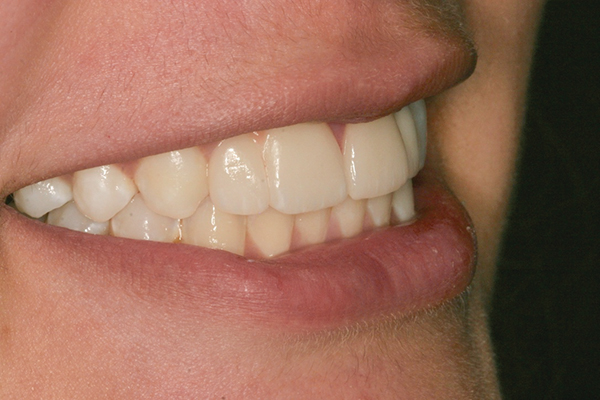

Using the wax-up as a guide, a composite restoration was fabricated for fused teeth Nos. 7 and 8 by roughening the affected area without pulpal exposure, etching the enamel, and applying primer and adhesive. Composite shade A1 was bonded to the mesial and distal surfaces, with gingival dark composite applied to the cervical “interproximal” region. The tooth was then carved to resemble two teeth, matching the width of the created tooth central to tooth No. 9 (Figure 4 and Figure 5). The patient and her family were very pleased with the result, and no postoperative sensitivity was reported.

Fig 4 and Fig 5. The fused tooth was carved to resemble two teeth, matching the width of the created tooth central to tooth No. 9.